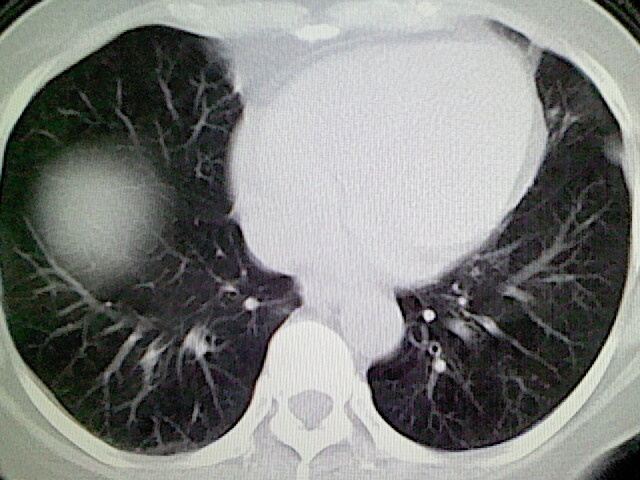

女,52岁,咳嗽,咳痰多日

左下肺陈旧纤维索条!

左肺舌段炎性改变

我见过几例,为炎症后纤维条索

慢性炎症后改变

考虑慢性炎性病灶粘连牵拉改变。

左肺舌叶纤维锁条病变。

左肺上叶下舌段炎症并局部胸膜反应。

左肺舌叶纤维索条影。

左肺舌叶段陈旧性病变

左肺舌段炎性反应。片子的质量太不好了。

左肺舌段炎性

炎性改变

左肺舌叶纤维索条影